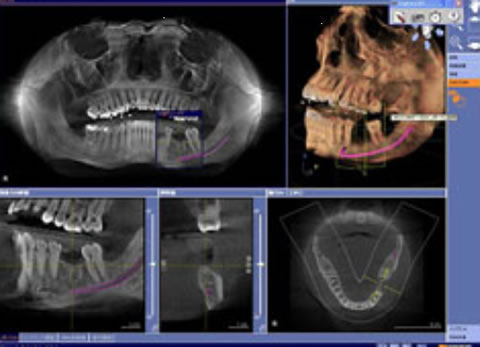

当院が導入しております最新の歯科用CT「SL」を使用することで、どの角度からでも口腔内の歯、骨格、神経など歯科治療に必要な情報を確認することが出来ます。また、従来のCTではデータ解析をするのに多大な時間を要し、診断可能になるまで14日以上ものロスがありましたが、このCTは撮影して数分後に口腔内を確認することが可能となっております。

インプラント治療計画ソフトウェア 複雑な治療計画をサポート

CGのインプラントソフトウェアは、神経管や骨格がビジュアル化され確認しやすく解剖学的な私見を必要とする患者様のインプラント治療に適したソフトウェアです。より正確なプランニングと埋入により安全性の確保を促し、不要なストレスが低減されます。治療状態を確認しインプラント埋入本数を増やすだけではなく、患者様へのプレゼンテーションにおいても3D画像により患者様への説明をサポートします。

インプラント設計診断分析

正確な診断の為の正確無比なCT撮影